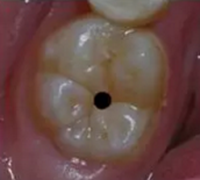

3、齲齒不一定像你看到的

當(dāng)你看到有個(gè)小小齲的時(shí)候,常常是這樣子的:

當(dāng)心“腹黑”齲齒,牙齒有個(gè)小洞也要補(bǔ)!

你不知道它里頭是啥樣子的,我來告訴你:

運(yùn)氣好的話,它是這樣子的:

你從外頭看上去,一樣也是個(gè)小黑點(diǎn),但其實(shí)人家躲在下面就快創(chuàng)業(yè)成功了!